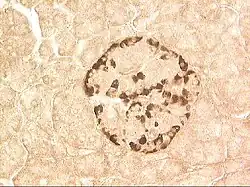

α-Кле́тки — один из видов клеток, образующих эндокринную часть поджелудочной железы.Таким образом, эти клетки являются одним из типов клеток, входящих в состав панкреатических островков. Альфа-клетки продуцируют гормон глюкагон, одним из эффектов которого является повышение уровня глюкозы в крови. Кроме этого, альфа-клетки панкреатических островков сходны по ряду биохимических и физиологических характеристик с нервными клетками: например, они содержат ацетилхолин[1]. При электронной микроскопии альфа-клетки выделяются благодаря характерным гранулам, содержащим плотное ядро, окружённое узким светлым ободком. Размеры гранул составляют около 230 нм. Они устойчивы к действию спирта, однако растворимы в воде; проявляют сродство к кислым красителям.

У грызунов альфа-клетки расположены преимущественно по периферии панкреатических островков, у человека островки имеют недостаточно упорядоченную структуру и альфа-клетки как правило обнаруживаются внутри них[2]. Кроме того, соотношение α-клеток мыши и человека отличается: доля α-клеток в островках мыши (18 %) ниже, чем у человека (38 %)[3].